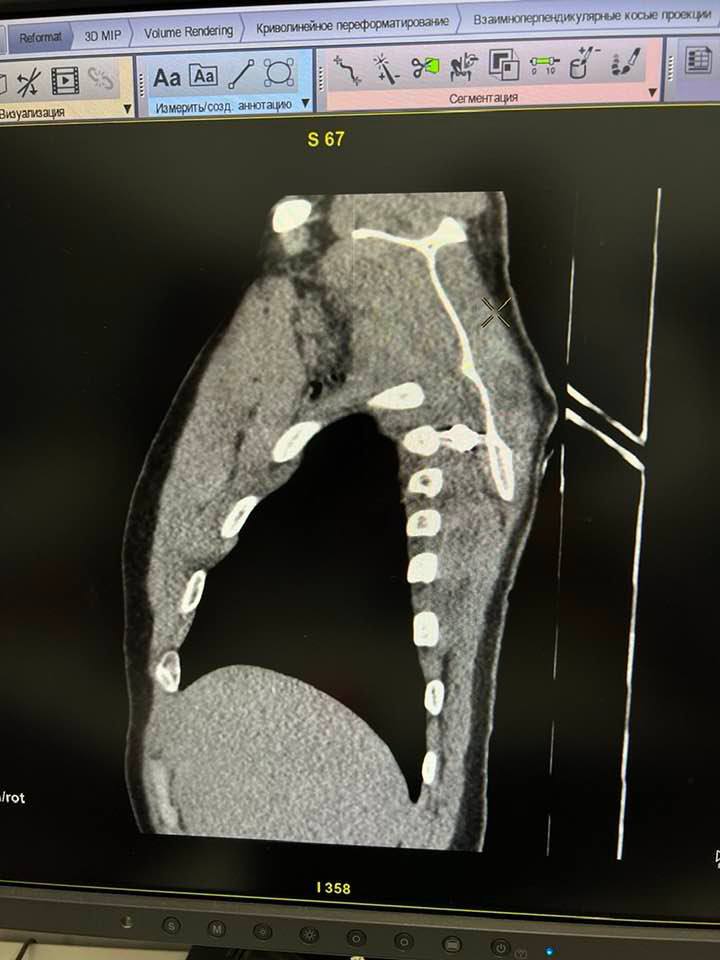

Одеські медики упішно видалили уламок гранати з грудної клітки військового

Там повідомили, що медики провели успішну операцію воїну ЗСУ та видалили уламок гранати з грудної клітки.